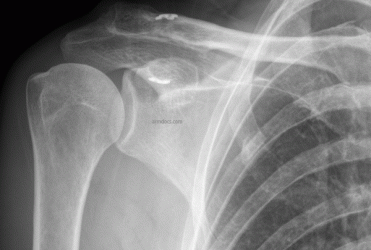

a. Displaced fracture of the outer end of the clavicle